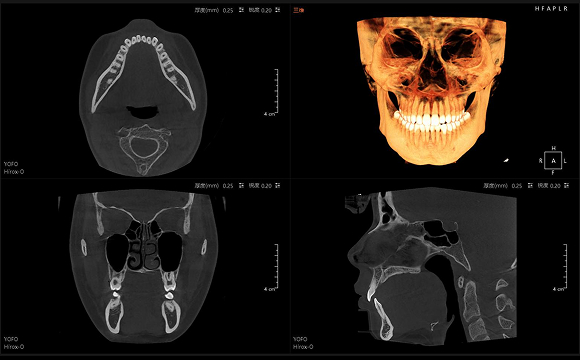

• CT

CT

• 3D全景

3D全景

只需一次单圈扫描即可获得CT、3D全景和3D正/侧位影像,并能同时生成3D TMJ视图

提高诊疗效率,避免过度检查,减少患者所受的辐射